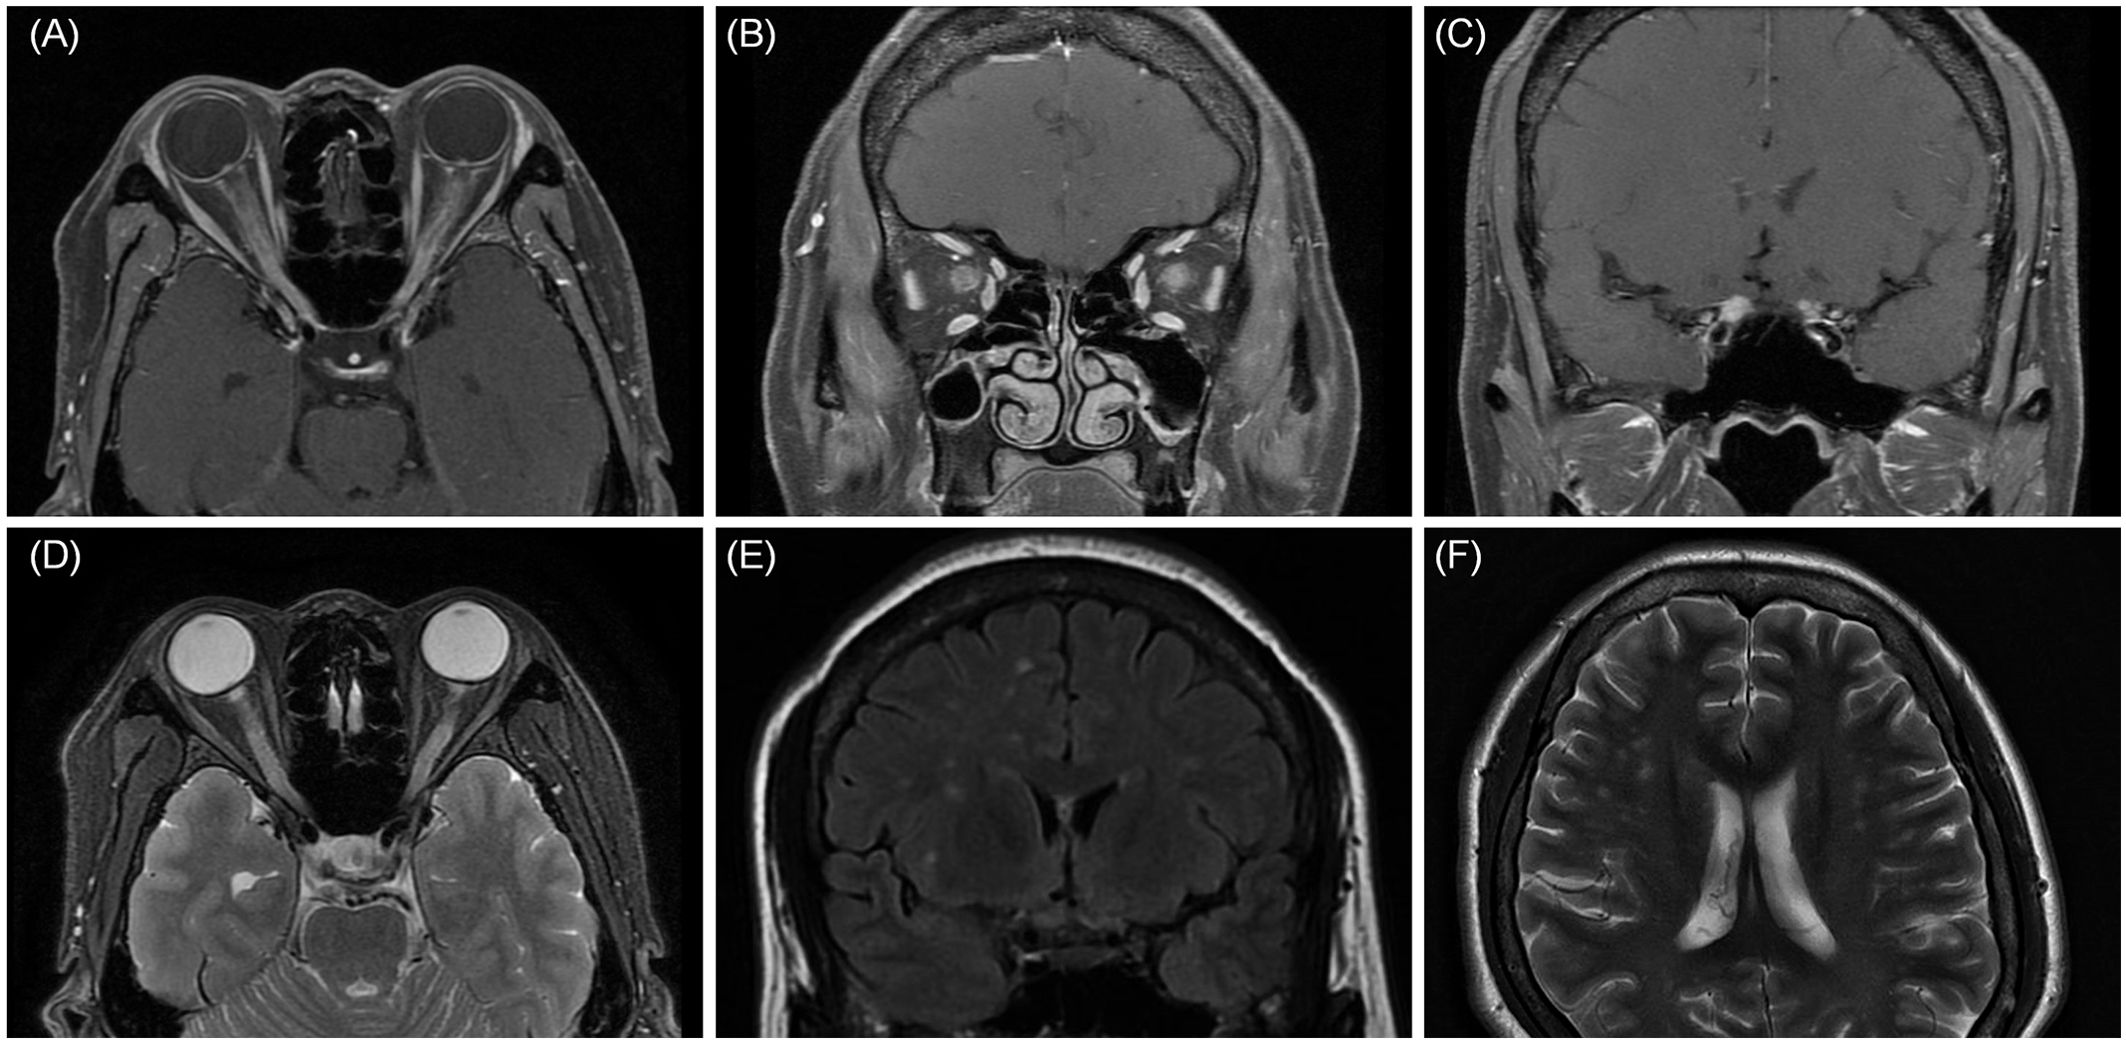

On April 18, 2022, a 39-year-old Chinese woman complained of subacute binocular vision reduction for 4 days and no light perception for 2 days. She reported having a fever and right upper quadrant abdominal pain, and a doctor determined splenomegaly 25 days prior. The highest temperature recorded was 38.5°C, and the fever diminished after symptomatic treatment in an outside facility; no cause was identified. One week after treatment of the fever, the patient’s orbital pain worsened on eye movement, and she experienced a headache that lasted for 15 days. Four days before coming to our clinic, she presented with a subacute bilateral decrease to 20/250 in both eyes. At our clinic 2 days later, both eyes showed no light perception. The patient denied any toxic substance exposure, trauma, autoimmune disease, or family history of neuropathy. Examination showed that both pupils were fixed and dilated, with diameters of 7.5 mm and 6.5 mm in the right and left eyes, respectively. Fundus examination revealed binocular peripapillary, perivascular haemorrhages; extensive deep retinal haemorrhages with severe optic disc swelling, with right eye greater than left; and dilated and tortuous retinal venules. Fluorescein angiography images showed leakages of the bilateral optic disc and peripheral capillaries. Optical coherence tomography showed bilateral optic disc swelling (Figures 1A–E). Magnetic resonance imaging (MRI) showed bilateral enhancement of the optic nerve sheath, optic nerve, and chiasm on the axial and coronal sides. Fat-suppressed T2-weighted sequences showed a hypersignal of the bilateral optic nerves and sheath. T2 imaging revealed asymmetric multifocal patches of a bright signal that involved the left and right frontal cortices and the periventricular white matter of both parietal lobes (Figures 2A–F). The brainstem and spinal cord were normal. The patient tested positive for the Epstein–Barr virus (EBV) antigen (595 U/mL) and the EBV capsid antigen (>750 U/mL). The patient’s IL-6 serum was elevated (84.9 pg/mL), and the number of monocytes was normal. Tests for white blood cell count, platelet count, calcium, liver function, erythrocyte sedimentation rate, C-reactive protein, serum IgG4, anti-Ro, anti-La, rheumatoid factor, antinuclear antibody titre, and thyroxine were normal. While intracranial pressure was normal (120 mmH2O), cerebrospinal fluid analysis revealed a mildly elevated protein of 414.6 mg/L and a normal white blood cell count of 6 × 106/L. The cerebrospinal fluid oligoclonal band was negative. A flow cytometric assay, which examines the biomarkers of central nervous system demyelinating diseases using live cell-based methods, showed that the MOG antibody was seropositive at a titre of 1:320, while the aquaporin 4 (AQP4) antibody was seronegative.

Figure 2. MRI axial (A) and coronal (B, C) showed bilateral enhancement of the optic nerve sheath, optic nerve, and chiasm. (D) Fat-suppressed T2-weighted sequences showed a hypersignal of the bilateral optic nerves and sheath. (E, F) Coronal and axial MRI was found to have multifocal patchy lesions in white matter of frontal cortex and the periventricular white matter.